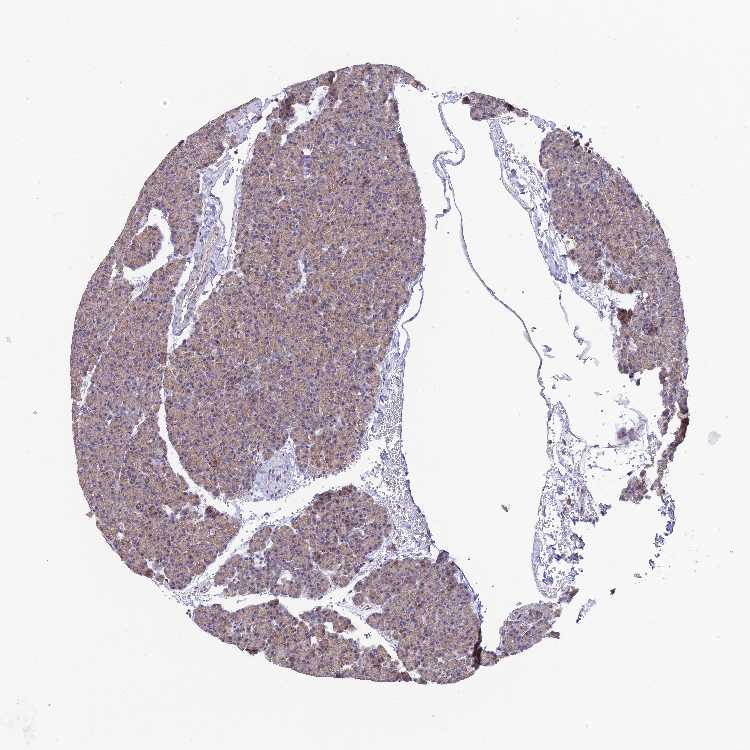

PANCREAS - Antibody stainingi

Antibody staining in the annotated cell types in the current human tissue is reported as not detected, low, medium, or high, based on conventional immunohistochemistry profiling in selected tissues. This score is based on the combination of the staining intensity and fraction of stained cells.

Each image is clickable and will lead to virtual microscopy that enables deeper exploration of all samples and also displays staining intensity scores, fraction scores and subcellular localization as well as patient and tissue information for each sample.

Antibody HPA038759Antibody HPA040515Antibody HPA045924

Exocrine glandular cells LowMediumMedium

Pancreatic endocrine cells -Medium-